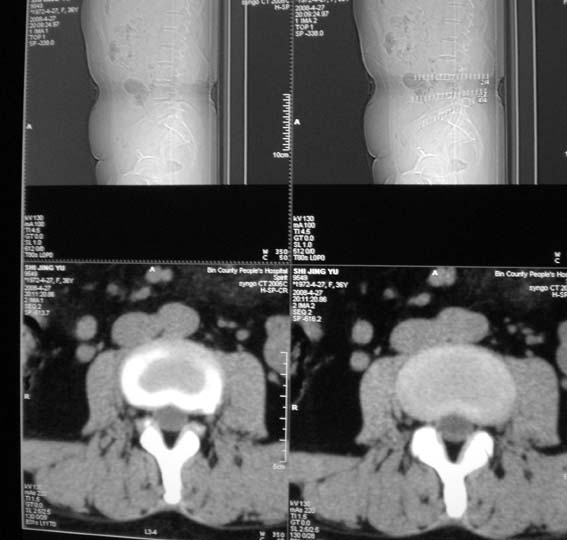

女,36岁,腰痛多年,坐久后,起身疼痛难忍。

考虑:1、腰5-骶1椎间盘突出(右旁中央型)。

2、腰5椎体下终板平面后缘后纵韧带钙化。

腰4/5椎间盘轻度膨出,腰5/骶1椎间盘突出(右旁中央型)伴局部椎间盘钙化。

腰4~5椎间盘轻度膨出,腰5~骶1椎间盘突出(右侧型)伴局部椎间盘钙化。

后纵韧带钙化。

腰4/5椎间盘轻度膨出,腰5/骶1椎间盘突出(右旁中央型)伴局部椎间盘钙化、右侧n根受压。